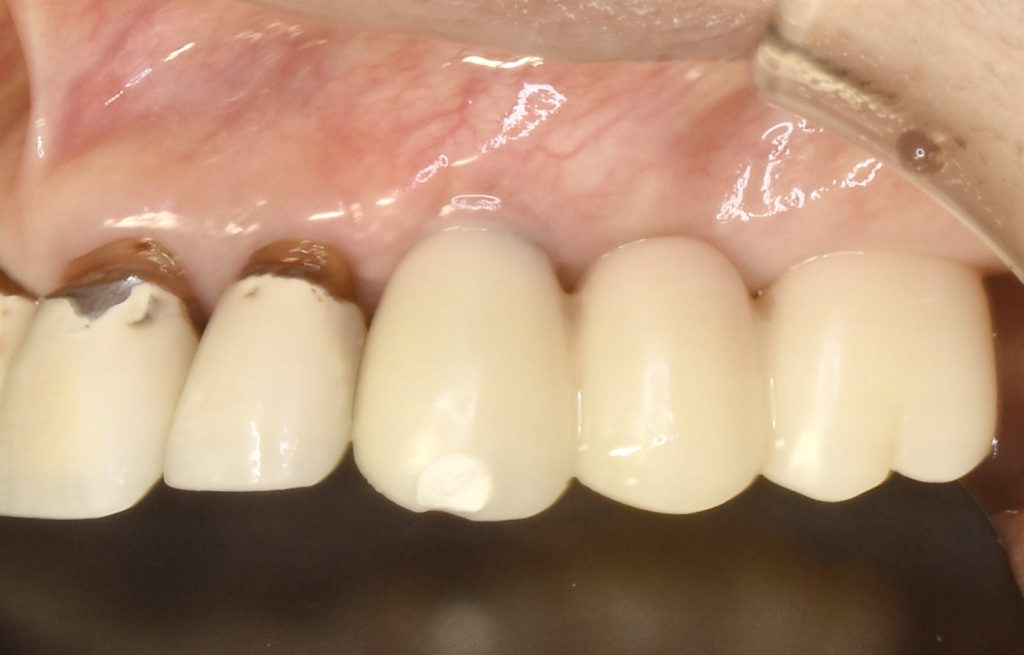

一味違う美しさと手入れしやすく、違和感の少ない形態を手に入れたい患者さんは是非当医院にお任せください。